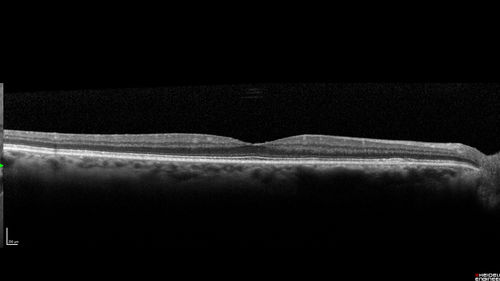

Chronic Endophthalmitis and Cystoid Macular Edema

VA 20/50 - Culture negative. Cleared with intravitreal antibiotics and decadron